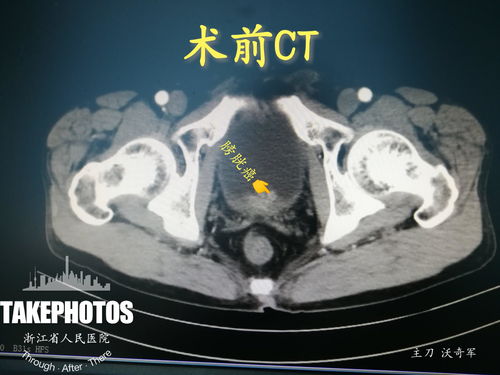

尿血,无痛,血尿,上火,泌尿外科

尿血-无痛血尿当上火,泌尿外科膀胱镜发现菜花样肿物

引言:被忽视的健康警报 在日常生活中,许多人发现尿液颜色变红或呈洗肉水样时,第一反应常将其归咎于“上火”。尤其是在没有伴随疼痛、发热等明显不适的情况下,“不痛不痒,应该只是上火了”的想法更为普遍。这种基于民间经验的自我诊断,可能导致对潜在严重健康问题的延误。事实上,血尿,特别是无